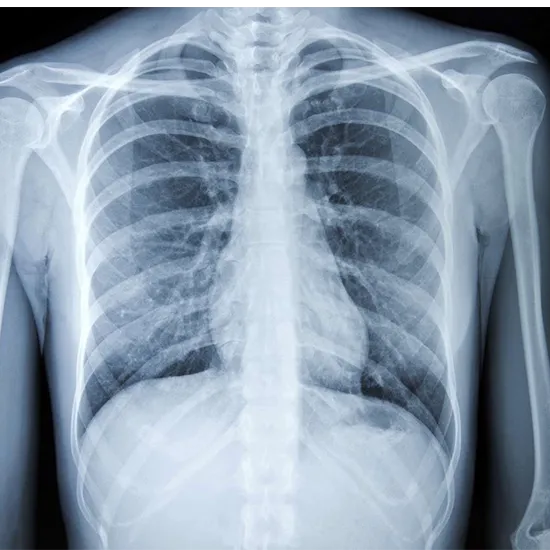

What is an X-ray Screening Chest Test?

The term "screening chest" refers to an imaging technique used to view the chest region. It helps identify any abnormalities in the thorax, the spinal cord, the rib cage, the lungs, the heart, or any other surrounding tissues and muscles.